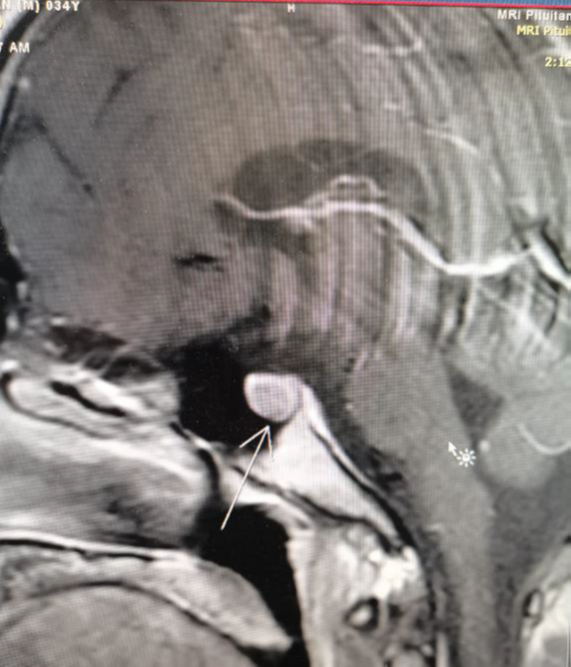

Our patient, Mr. X, a 34-year-old male, was referred to an endocrine clinic (in King Hussain Medical Center) to assess his thyroid status. Upon evaluation, he was anxious and irritated, and his sister said he had some behavioral changes for the last few months. He was usually calm and friendly, she said he lost weight despite his increased appetite. His past medical history was significant for epilepsy and minor cardiac anomalies (atrial septal defect and atrioventricular canal). During examination, he had a small firm goiter with no bruit or thrill on palpation. He also had tremors of outstretched extremities, but no opthalmopathy which can be related to thyroid disorders, galactorrhea, or acromogelic features. His heart rate was 105, and his blood pressure was 127/80. His laboratory investigations showed a thyroid function test (tft) with elevated TSH level 17 (normal range: 0.34–5.6 μU/L) and elevated free thyroxine level 2.46 (normal range: 0.7-1.8 ng/dl). We ran the test again, and it revealed similar readings. Previous thyroid function tests were normal, so a thyrotoxic condition was considered. A beta-blocker was prescribed to the patient, and it had a dramatic effect on controlling his symptoms. Ultrasonography showed a mild goiter with hypervascularity, and the thyroid scintigraphy scan showed thyroid enlargement with hypervascularity (Figure 1), so a diagnosis of hyperthyroidism was confirmed. An auto-antibody panel was sent, and it came back negative. The sex hormone binding protein was a high normal 51.97 nmol/l (range 18.3–54.1), the alpha subunit wasn't done due to unavailability. Growth hormone and prolactin were normal. In addition, pituitary magnetic resonance imaging (MRI) (Figure 2), (Figure 3), (Figure 4) was done, and it showed a microadenoma of 9.9*8.4 mm dimensions with no pressure effect on the pituitary stalk and optic chiasm. He underwent visual perimetry and his visual fields were normal. As we suspected a TSH-secreting pituitary tumor, a somatoastain analogue was given to the patient for both diagnostic and therapeutic purposes.4–7 Tsh level showed significant suppression (15 to 5 normal range: 0.34–5.6 μU/L), four weeks following the somatostatin analogue injection. As surgery is the first-line treatment for Tsh-oma, his case was discussed with the neurosurgeons, and the patient was sent for surgery. Before surgery, his heart rate was controlled by beta blockers, and then he underwent transsphenoidal surgery by an expert neurosurgeon with no significant postoperative complications.8

Figure 1 Sagittal pituitary MRI.

Figure 2 Coronal pituitary MRI.